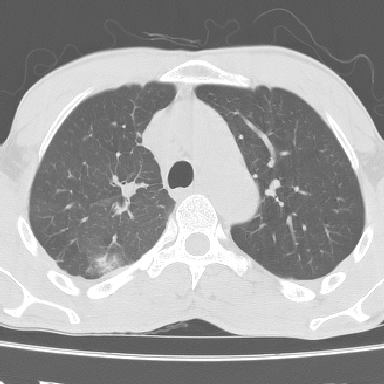

以下是引用lpc0ct在2006-11-28 16:12:00的发言:[br]大家图文并貌分析的太全面了,没有可说的,同意 [br] 右肺上叶中心型肺癌伴肺门、纵隔淋巴结转移.[br]

以下是引用dyqct在2006-11-28 16:00:00的发言:[br]右肺上叶中心型肺癌伴肺门、纵隔淋巴结转移。[br][br]